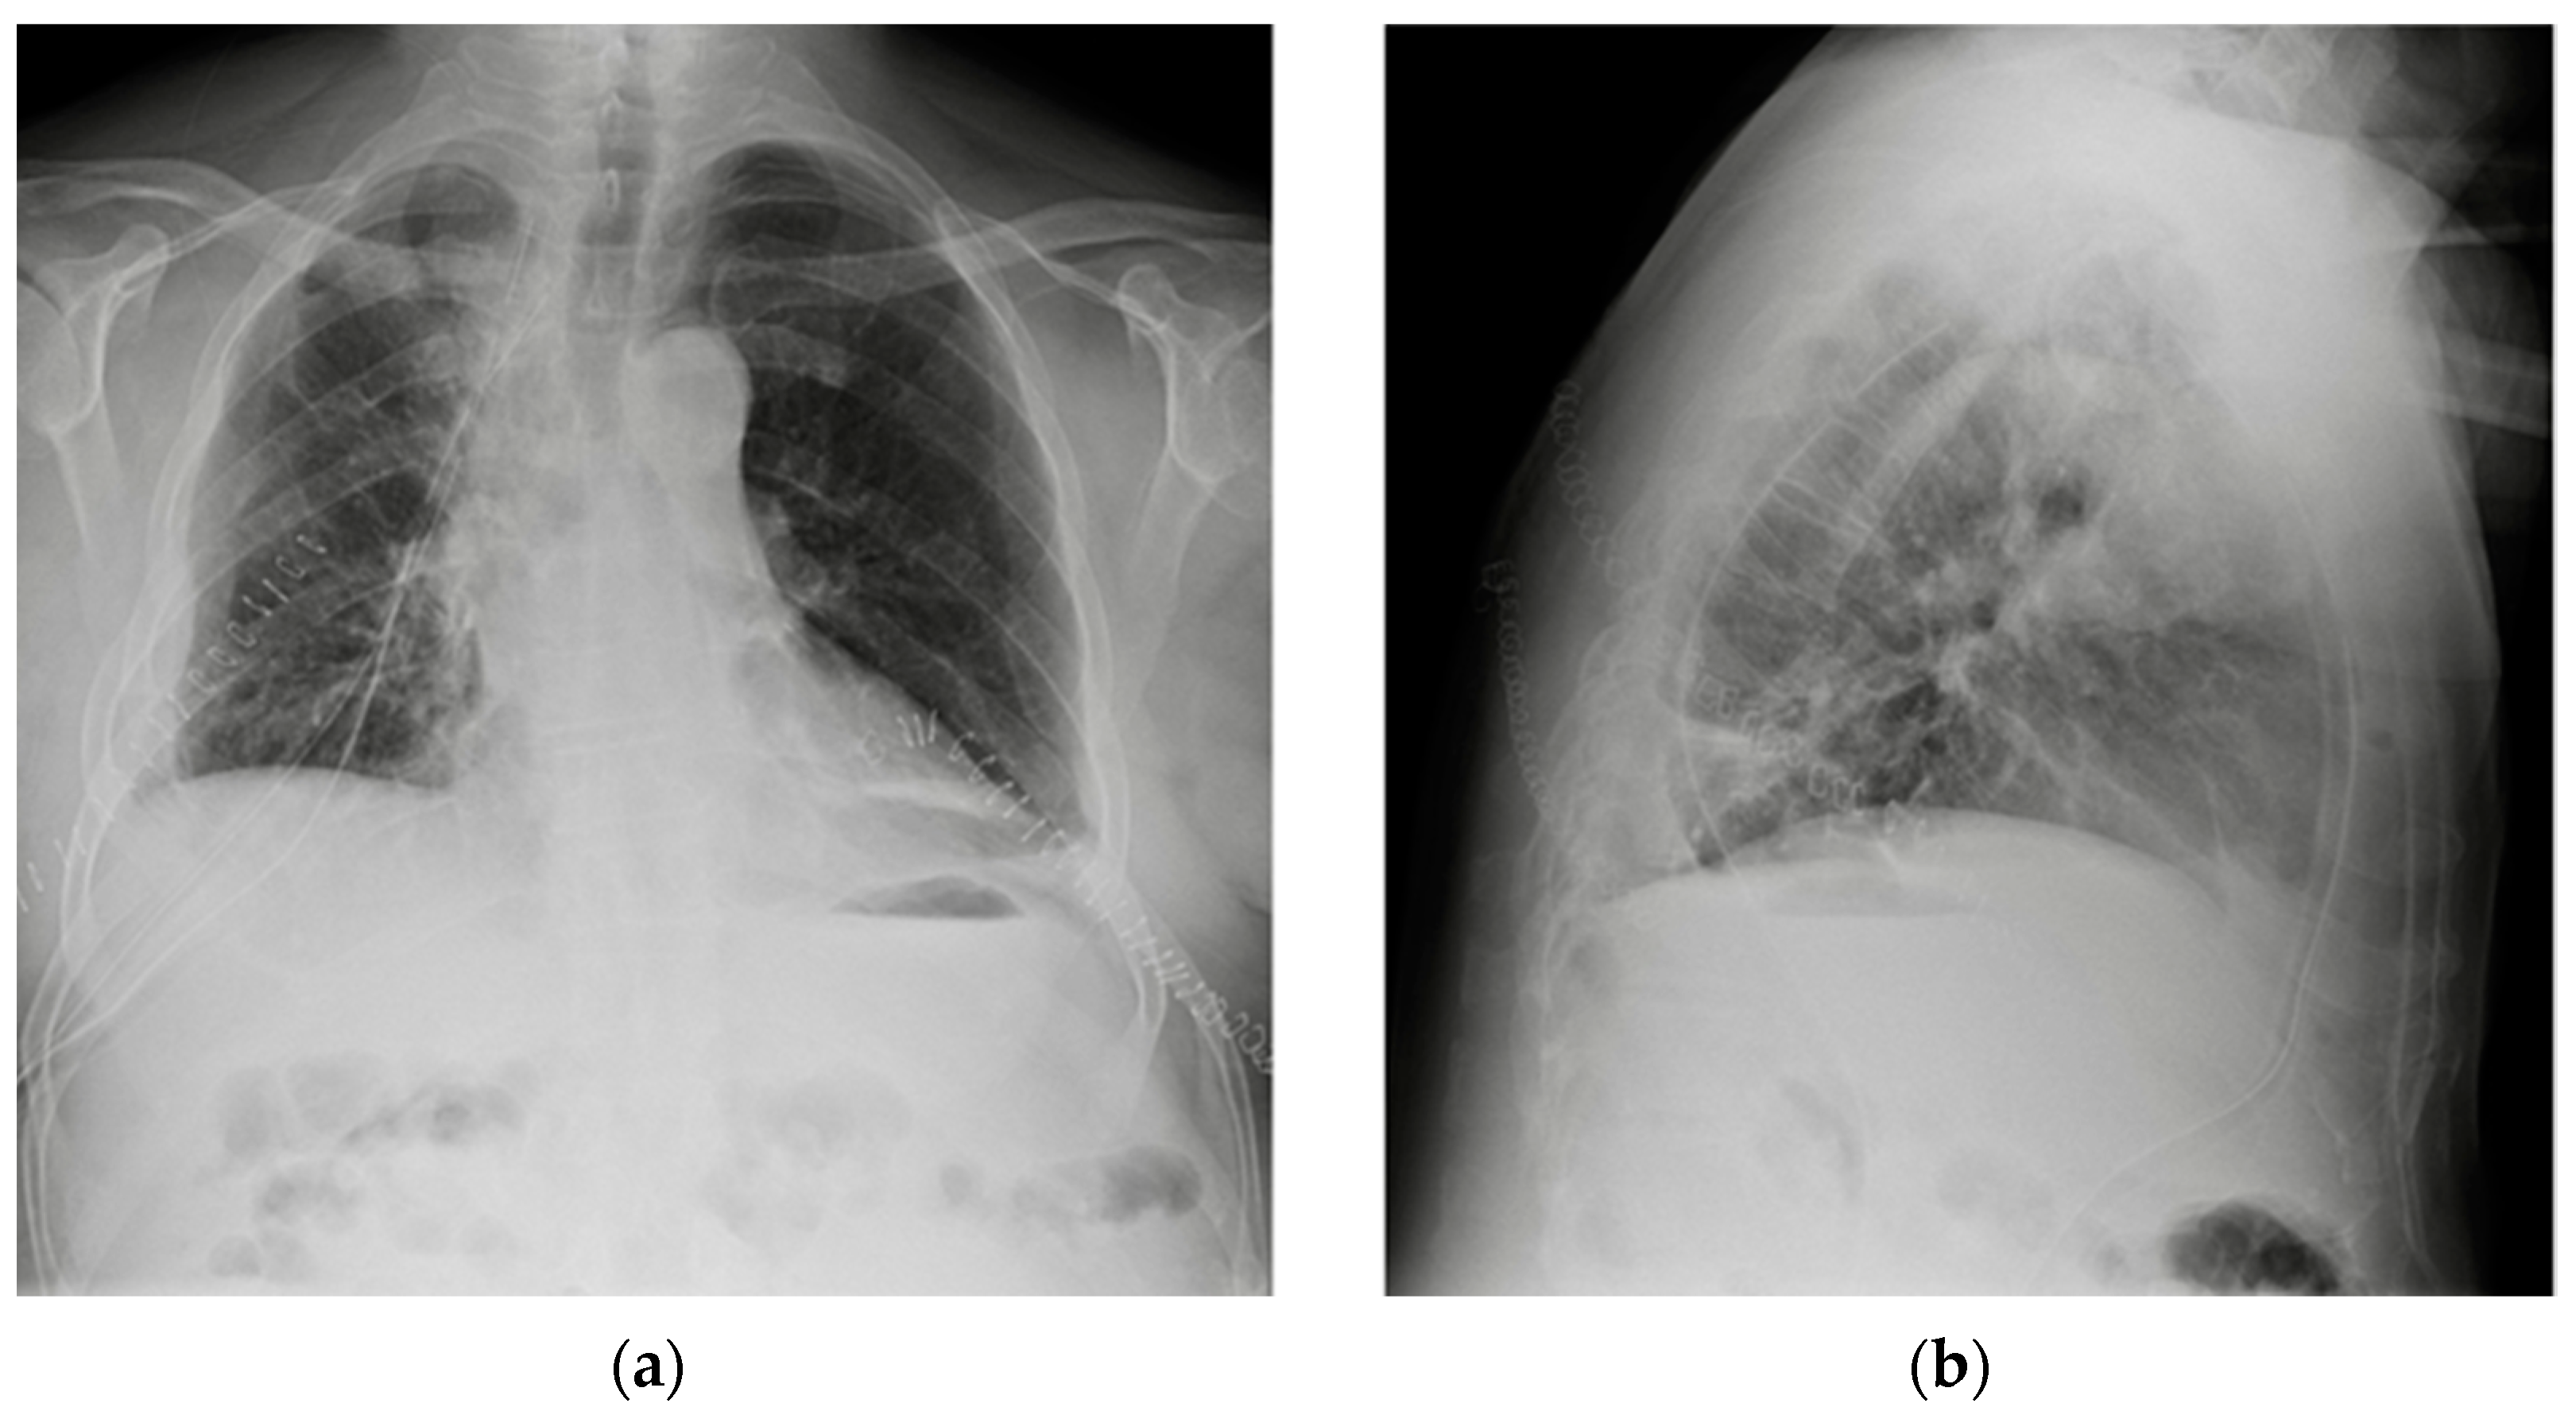

Figure 30.

Images of a right pleural effusion before (a) and after (b) drainage through an inferior-posterior chest tube. Right enlargement of the upper mediastinum is also present.

Figure 31.

Image of a pig-tail chest tube inserted through the right lateral chest wall draining a right basal pulmonary effusion. Note that in this case, the lateral view (b) depicts the tube loops more clearly than PA view (a); also, there seems to be an effect given by the uplifting of the arms in the lateral view, with the insertion point of the tube being dragged upward and so “emphasizing” its looping appearance.